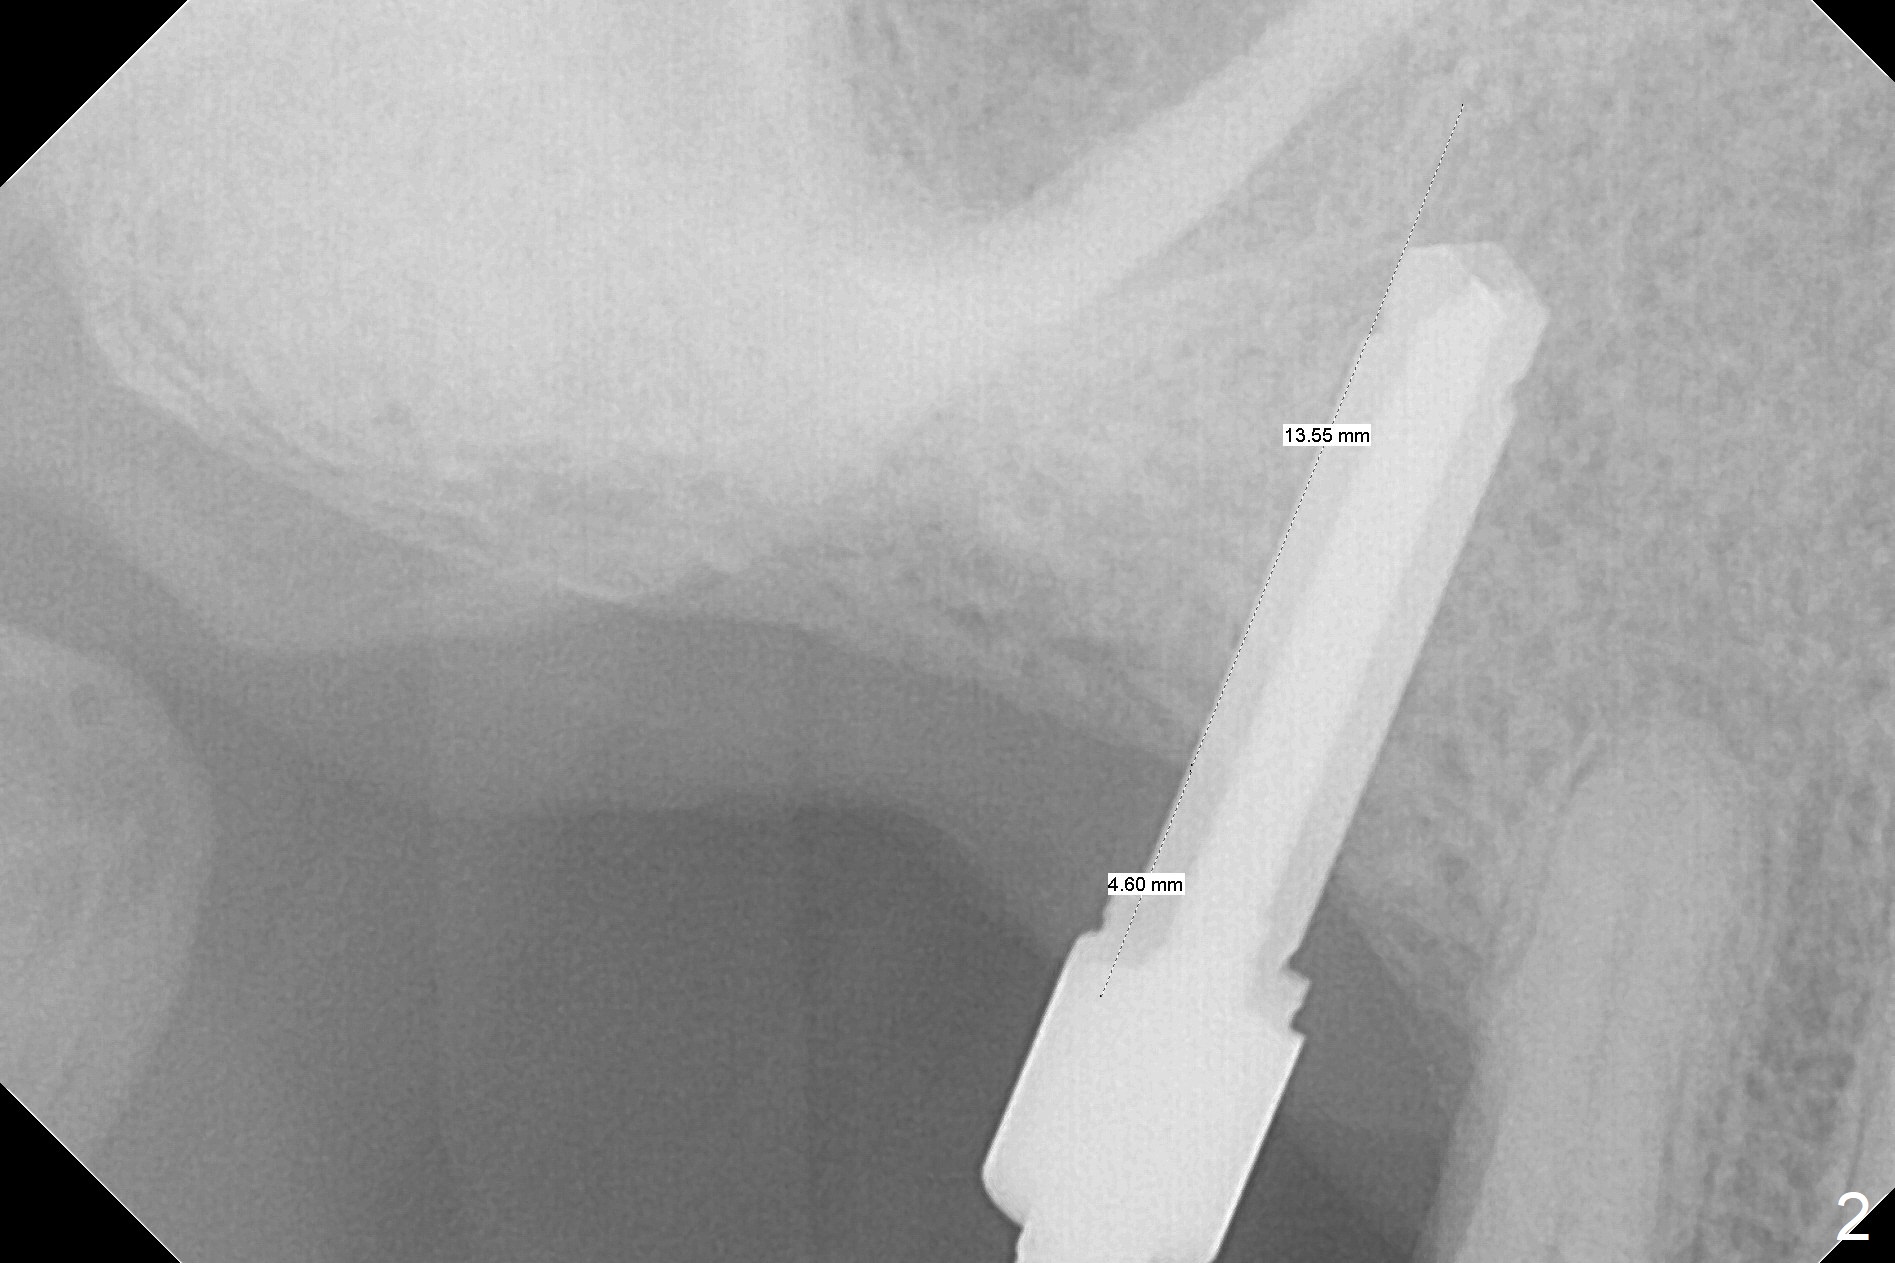

Since the ridge crest at #3 is narrow, Tatum bone scalpels are used to get access and initiate bone expansion, followed by bone blades and RT 2.  It seems that the osteotomy starts mesially; bone height being increased (Fig.1).  When the apical end of the osteotomy tilts mesially, more bone height is obtained.  Drills are alternatively applied because of the hard bone (Fig.2).  A 4x13 mm UF implant is placed initially with the distal threads unburied (Fig.3, >50 Ncm).  With further seating of the implant, a 5.5x5(4) mm abutment is used (Fig.4), which closes the access.  No suture is warranted.  An immediate provisional is fabricated for the patient's comfort and psychological effect.  In fact, the abutment cuff changes to 5 mm prior to temporarization.  There appears no bone loss <4 months postop (Fig.5).  Pulpitis develops at #4 due to DO caries 1 year 5 months post cementation (Fig.6 *).  The crown at #3 is removed for easy and conservative distal carious removal and Cavit temporary restoration to prevent sodium hypochlorite leakage.  Then occlusal access is made for pulpotomy.  When RCT finishes, no crown will be made, but occlusal reduction is required.    The patient returns for RCT 1 month later (Fig.7,8). Cavit remains in place (Fig.7 C).  Although 2 threads are exposed distal (Fig.8 arrow), there is no sign or symptom of periimplantitis, which may be related to the thick gingiva (arrowhead).  Return to Upper Molar Immediate Implant, IBS, #14 (Tissue Punch) Xin Wei, DDS, PhD, MS 1st edition 08/25/2017, last revision 09/08/2019